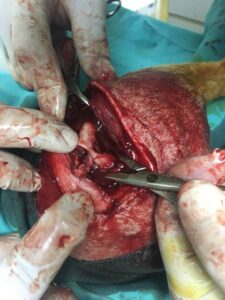

Operationsfotos

Von unserem Patienten (siehe vorletzten Bericht) haben wir hier einige Fotos der erfolgten, erfolgreichen Operation: